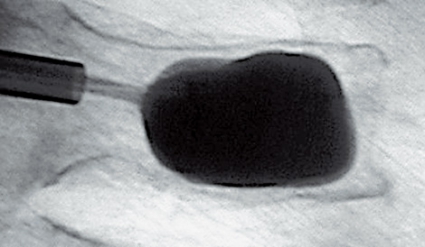

Grundprincipen bakom metoderna är att man genom en perkutant insatt kanyl fyller den frakturerade kotkroppen, eller fraktursystemet i sakrum, med bencement (polymetylmetakrylat) [7-14, 16, 17], så att fraktursystemet stabiliseras, ryggsmärtan reduceras och patientmobiliseringen underlättas. Vid vertebro- och sakroplastik cementerar man frakturerna i befintligt frakturläge (Figur 1 och 2), medan man vid kyfoplastik för in en tom ballong i kotan. Ballongen blåses sedan upp, och målet är att reducera felställningen i kotan före cementeringen (Figur 3). Denna teknik ter sig åtminstone i teorin tilltalande [14, 16]. För närmare beskrivning av metoderna hänvisas till kompletterande litteratur [6-14, 16, 17]. Såväl vertebro- som kyfoplastik kan ge upphov till en mängd komplikationer, såsom cementläckage i segmentella vener, cementläckage utanför kotan och in i spinalkanalen (med i enstaka fall parapares som följd), migration av cementkroppen efter kyfoplastik, revbensfraktur, septisk spondylit, lungödem och hjärtinfarkt. Det har hittills inte presenterats någon studie som visat att den ena metoden skulle ge färre komplikationer än den andra. Förekomsten av komplikationer måste också tas med i beaktande när man gör hälsoekonomiska utvärderingar av metoderna.

Sedan ett decennium har behandlingsförsök gjorts med cementering även av denna frakturtyp under ledning av genomlysningsröntgen eller DT [6]. I dag finns emellertid en begränsad evidens för behandlingens effektivitet. Frey et al beskriver i en okontrollerad, prospektiv observationsstudie, inkluderande 52 konsekutiva patienter med en medelålder på 76 år, smärtreduktion i majoriteten av fallen vid sakroplastik av osteoporotiska insufficiensfrakturer [17]. Vid närmare genomgång visar det sig att tidpunkten för smärtreduktionen är oklar. Då detta är en okontrollerad studie kan man ställa sig frågan om förbättringen snarast motsvarar naturalförloppet efter en sakrumfraktur. I dag finns oss veterligen inga hälsoekonomiska beräkningar som värderar metoden.